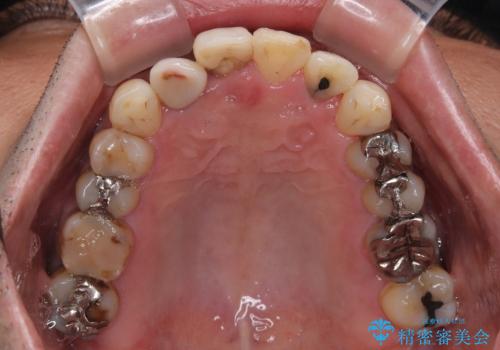

治療途中で海外に長期滞在することとなり、5年近く帰国することができなかったため、治療期間は非常に長いものとなりました。

内側に転位していた前歯は、矯正治療では治しきることができませんでしたが、幸いにもオールセラミッククラウンに置き換える予定であったため、希望通りの仕上がりとなりました。